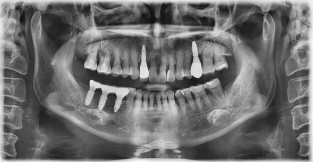

전체어금니

치료기간 : 2022-03-05 ~ 2022-10-01

1. 상기 x-ray 이미지 모두 동일한 해당 의료기관에서 진료한 환자입니다.

2. 상기 x-ray 이미지 모두 동일 인물의 것입니다.

3. 치료 전 이미지는 2022-03-05에 촬영했으며, 치료 후 이미지는 2022-10-01에 촬영하였습니다.

4. 상기 x-ray 이미지 모두 동일 조건에서 환자분의 동의를 받아촬영되었습니다.

* 임플란트 시술은 환자분의 상태(고혈압, 당뇨 등)에 따라 부작용이 있을 수 있으니, 반드시 전문의와 상담이 필요합니다.

* 임플란트 수술 부작용

: 수술 후 출혈, 교합, 통증, 붓기, 염증 등의 문제점이 발생할 수 있습니다.)

* 본 이미지들은 의료광고법을 준수하여 게시하였으며, <의료법 제 56조 제2항 제7호>에 의거하여 개개인의 신체 상태와 질병 진행도 등 여러 요인에 따라 치료 효과가 상이하기에 진료계획 또한 달라질 수 있음을 고지해드립니다.